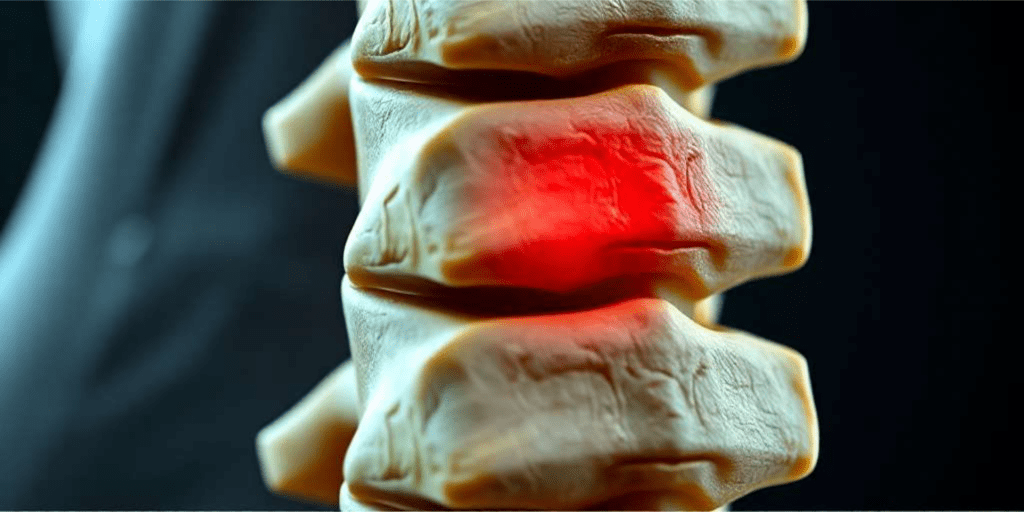

Por qué duele la espalda baja: causas de la lumbalgia

El dolor de espalda baja, también denominado lumbalgia o lumbago, afecta a ocho de cada diez personas a lo largo de su vida y supone

Pinzamiento Lumbar: Soluciones Efectivas para el Dolor Ciático y de Espalda

Pinzamiento Lumbar: Soluciones Efectivas para el Dolor Ciático y de Espalda ¿Sufres de dolor en la espalda o en la pierna desde hace meses? ¿El